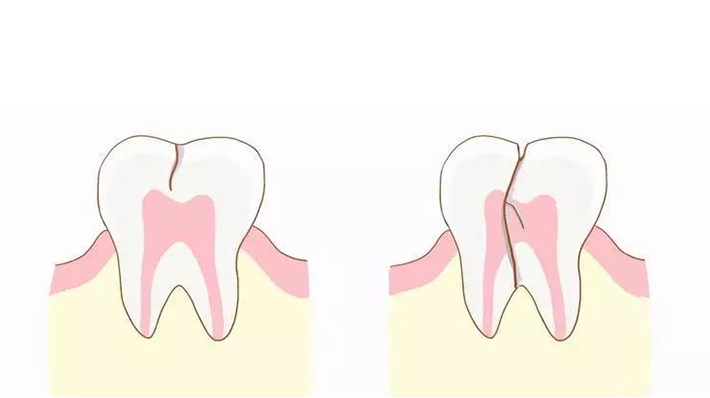

科普 | 你若对我置之不理,我必将“……